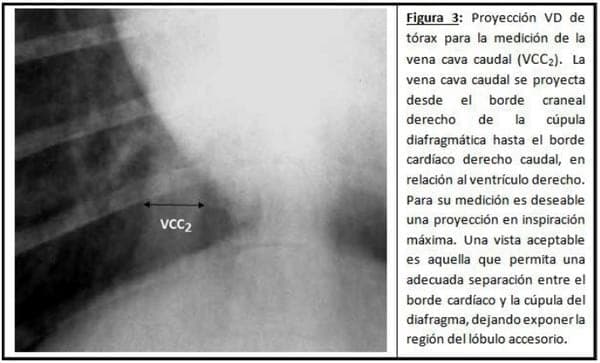

Radiología Toráxica: Las determinaciones radiológicas se realizaron sobre las incidencias laterolateral derecha (LLD) y ventrodorsal (VD). Se utilizó un equipo LADEM 300 con una técnica que mantuvo como constantes el miliamperaje (100 mA) y el tiempo de exposición (0.04 seg) y que varió el kilovoltaje de acuerdo al espesor del tórax de cada muestra. Se midieron, en base a parámetros preestablecidos, las siguientes estructuras: Eje cardíaco largo (EL) y eje cardíaco corto (EC) (Ver Figura 1); Vena cava caudal sobre RX LLD (VCC1 en Figura 2); Vena cava caudal sobre RX VD (VCC2 en Figura 3); Largo de la 5ta vértebra toráxica (L5ta) y alto de la 5ta vértebra toráxica (A5ta) (Ver Figura 4); Diámetro traqueal dorsoventral (Ver Figura 5); Arteria pulmonar craneal (APCr), vena pulmonar craneal (VPCr) y cuello de la 4ta costilla (C4ta) (Ver Figura 6); Arteria pulmonar caudal (APCa), vena pulmonar caudal (VPCa) y cuerpo de la 9na costilla (C9na) (Ver Figura 7). Se establecieron, a su vez, las siguientes relaciones: VHS; EL/EC; L5ta/A5ta; VCC1/VCC2; L5ta/VCC1; L5ta/VCC2; C4ta/APCr; C4ta/VPCr; C9na/APCa; C9na/VPCa; L5ta/T.

Parámetros Objetivos en la Evaluación Radiológico del Aparato Cardiovascular - Image 3